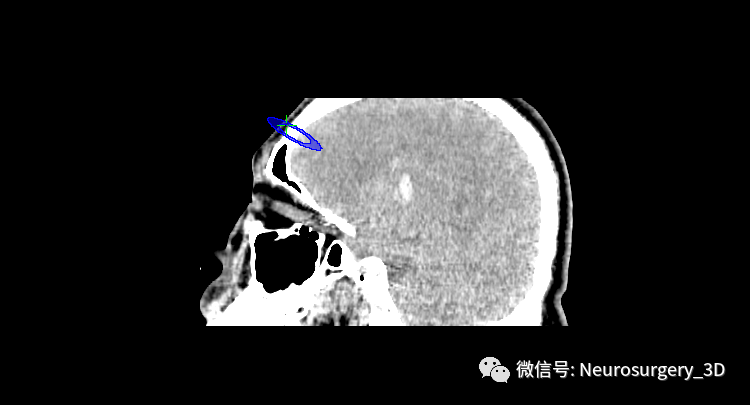

1、利用Ruler测量出穿刺血肿靶点至穿刺外口的距离,并设计出穿刺路径顺血肿长轴走形在血肿中心(并非如下图所示所有穿刺路径均与矢状面平行、请注意穿刺深度),避开颅内重要结构如额窦、上矢状窦等。

入颅点避开了额窦、上矢状窦

2、建立穿刺导管